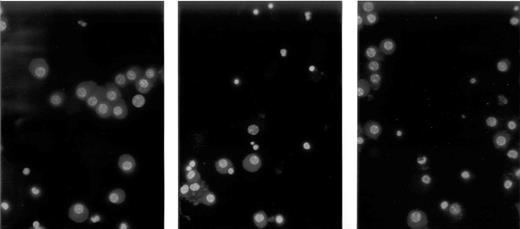

Results: Normal BMSC inhibited the growth of myeloma cells while myeloma BMSC improved it. As to U266, S+G2% of myeloma cells in normal BMSC group and myeloma BMSC group were 55.5±4.0% and 65.4±4.5%(p<0.05)respectively. The ratio of apoptotic cells were 3.92±1.83% and 0.86±0.58%(p<0.05)respectively(figure1 from left to right: U266, U266+normal BMSC, U266+myeloma BMSC, red: apoptotic cells). The level of IL-6 in the supernate were 1236±146.2pg/ml and 1661±161.5pg/ml(p<0.05)respectively. After co-cultured with normal BMSC and myeloma BMSC, S+G2% of freshly separated myeloma cells were 5.2±4.1% and 15.9±5.5%(p<0.05)respectively. The ratio of apoptotic cells were 18.7±7.8% and 8±3.9%(p<0.05) respectively (figure2 from left to right: fresh myeloma cells, fresh myeloma cells+normal BMSC, fresh myeloma cells+myeloma BMSC, red: apoptotic cells). The level of IL-6 in the supernate were 1621.2±121.1pg/ml and 2151.1±170.4pg/ml(p<0.05)respectively. The function of four adhesion molecules was different in the co-culture system. Anti-CD11a hardly affected the growth of myeloma cells. But anti-CD29 and anti-CD44 showed their significant inhibition to the growth of myeloma cells, including the decrease of supernatant IL-6 level, percentage of phase S+G2 and the increase of apoptotic cells (fresh myeloma cells). Anti-CD49d indicated partial inhibition, but no significant change.